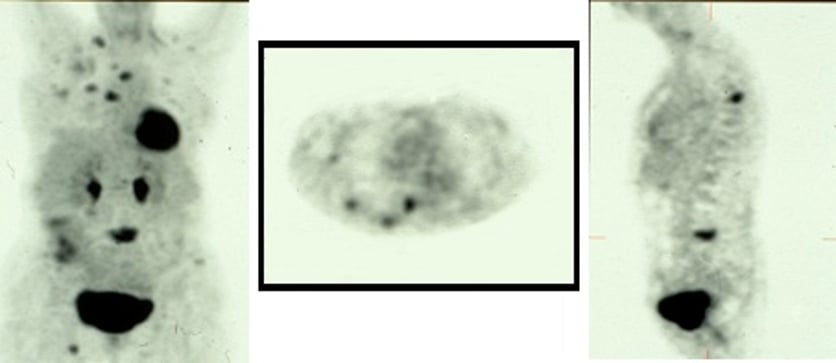

Somatostatin receptor scintigraphy (SRS)

SRS is a well-established functional technique for the imaging or NETs. Receptors for somatostatin and analogs have been identified on many cells of neuroendocrine origin. Of the five different subtypes of somatostatin receptors known to date, subtypes 1 and 2 appear to be the most frequent. The latter is the main target for visualization of NETs by SRS. The most commonly used somatostatin analog is octreotide, which is labelled with 111Indium, using the chelator diethylene-triamine-pentaaceticacid (DTPA) to produce 111Indium-DTPA-octreotide which is available as a commercial product - Octreoscan®. Other tracers are 111Indium-DOTA-TOC, 111Indium-DOTA-NOC and 111Indium-DOTA-TATE.

Somatostatin receptor scintigraphy (SRS)  Somatostatin receptor scintigraphy (SRS)

Metaiodobenzylguanidine (MIBG)

MIBG, a catecholamine analog, labelled with 123I or 131I, is a well-established tracer for scintigraphic visualization and treatment of tumors originating from the neural crest. That includes mainly phaeochromocytomas, paragangliomas, but also NETs, such as carcinoids. The sensitivity is lower than for SRS for GEP-NETs with a sensitivity of somewhere between 40-50%. In comparative studies the sensitivity of SRS to detect NETs exceeded that of MIBG scintigraphy.